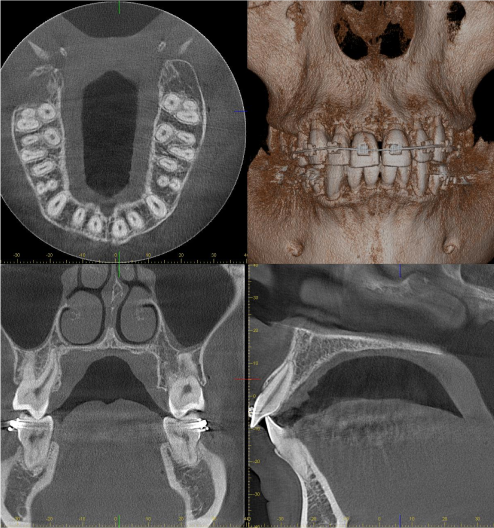

Конусно-променева комп’ютерна томографія

Дослідження, яке надає тривимірні дані, що позбавляє цей метод недоліків рентгенографії, оскільки відсутні проєкційні накладання та спотворення, характерні для двовимірних досліджень. Променеве навантаження при КПКТ більше, ніж під час інших досліджень для стоматологічних потреб, але при цьому воно надає незрівнянно більше достовірної інформації. Крім того, сучасне обладнання дозволяє максимально зменшити дозове навантаження за рахунок зменшення розмірів ділянки обстеження та зміни параметрів експозиції відповідно до мети обстеження.